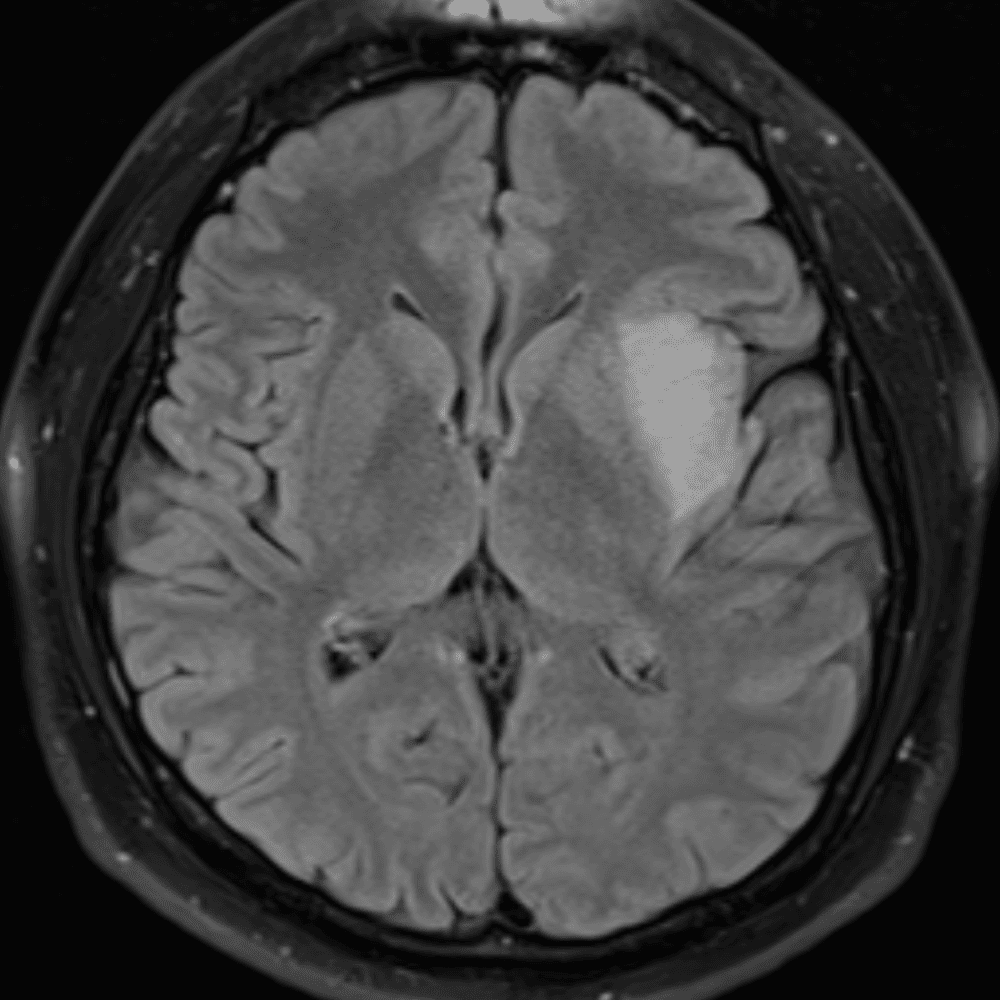

๋‹น์ง ์‹œ ํ”ํžˆ ๋ณผ ์ˆ˜ ์žˆ๋Š” ์‚ฌ๋ก€์˜ ์ „ํ˜•์ ์ธ ์˜ˆ๋ฅผ ํฌํ•จํ•ฉ๋‹ˆ๋‹ค.

39 ์‚ฌ๋ก€

์—ฐ์Šต

๋ฏธ๋ฌ˜ํ•˜๊ฑฐ๋‚˜ ์–ด๋ ค์šด ์‚ฌ๋ก€์™€ ์ผ๋ถ€ ์ •์ƒ ์‚ฌ๋ก€๋ฅผ ํฌํ•จํ•˜์—ฌ ๋‹น์ง์„ ์‹œ๋ฎฌ๋ ˆ์ด์…˜ํ•ฉ๋‹ˆ๋‹ค.

50 ์‚ฌ๋ก€